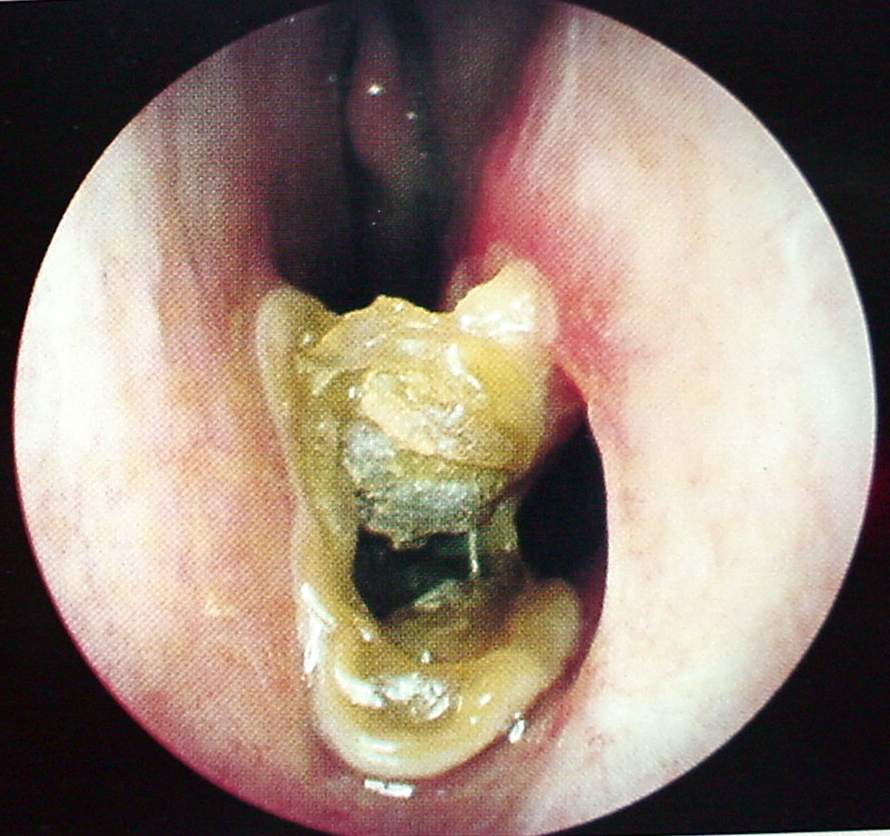

Nose and PNS Clinical Photos for Static Stations